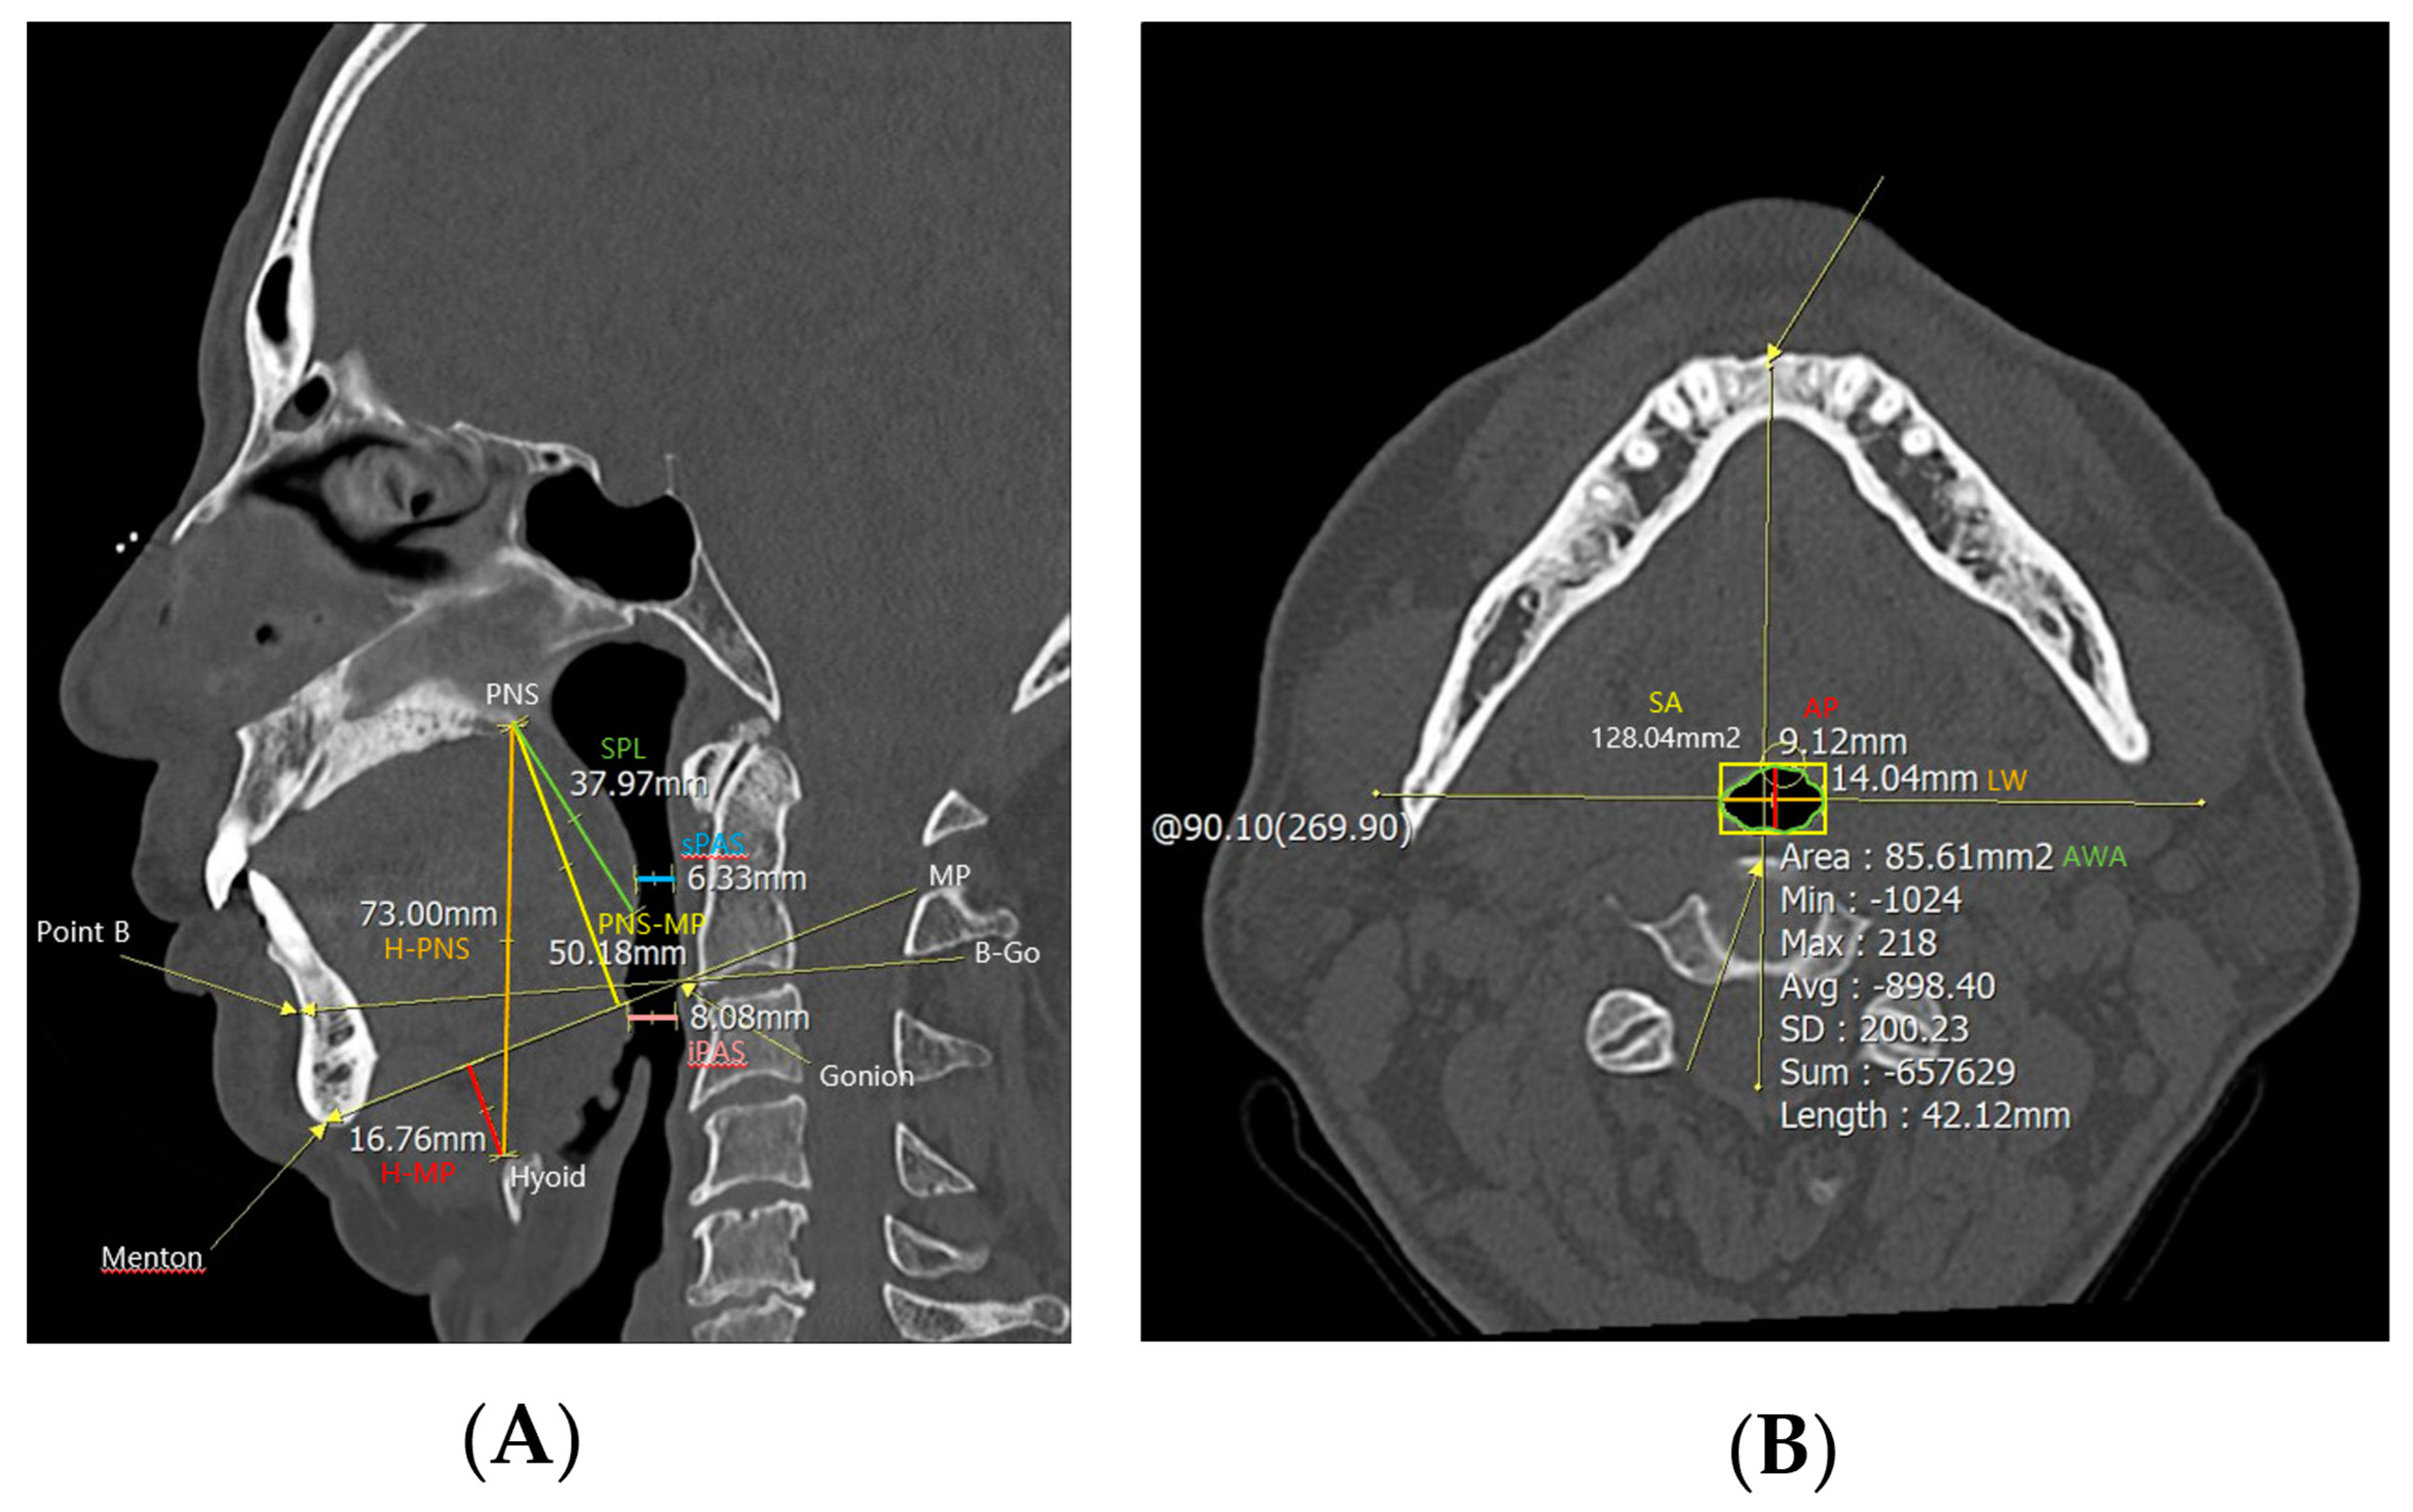

PNS CT was performed to examine anatomical abnormalities of the upper airway. In the midsagittal view of CT, cephalometric parameters such as H-PNS (distance between the hyoid bone and posterior nasal spine), posterior nasal spine-mandibular plane (distance between posterior nasal spine and mandibular plane, PNS-MP), H-MP (distance between the hyoid bone and mandibular plane), superior posterior airway space (distance between the posterior wall of the pharynx and the soft palate parallel to the B-Go plane, sPAS), inferior posterior airway space (distance between the posterior wall of the pharynx and the base of the tongue parallel to the B-Go plane, iPAS), and SPL were measured (Figure 1). And in the axial view of computed tomography, the anterior–posterior width (AP), lateral width (LW), square area (SA), and airway cross-sectional area (AWA) of the airway were measured at the level of the anterior–inferior corner of the second cervical vertebra [10].

Figure 1.

Cephalometric parameters measured using PNS CT. H−PNS, PNS−MP, H−MP, sPAS, iPAS, and SPL were measured in (A) the midsagittal view of the PNS CT, and AP, LW, SA, and AWA were measured in (B) the axial view. Abbreviations: H−PNS, hyoid–posterior nasal spine; P–MP, posterior nasal spine–mandibular plane; H–MP, hyoid–mandibular plane; sPAS, superior posterior airway space; iPAS, inferior posterior airway space; SPL, soft palate length; AP, anterior–posterior width; LW, lateral width; SA, square area; AWA, airway cross–sectional area.